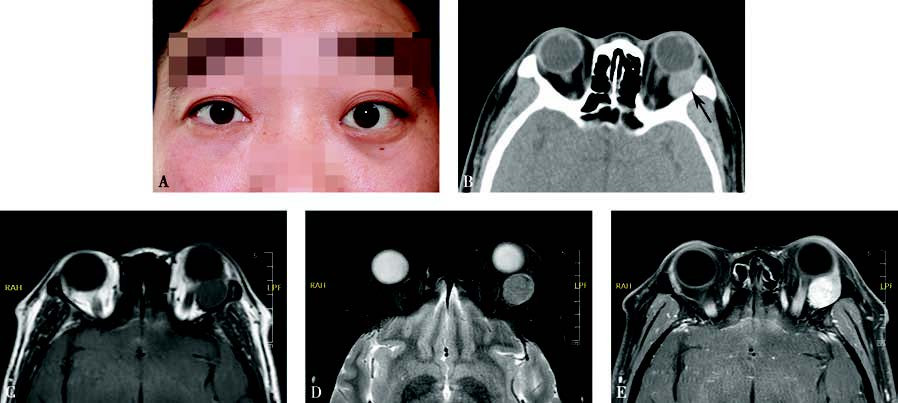

Figure 1 Appearance and imaging of pleomorphic adenoma of the lacrimal gland

A. A photograph of a patient with pleomorphic adenoma of the left lacrimal gland, showing left proptosis and downward displacement of the eyeball.

B. Axial CT imaging shows an isodense mass in the left lacrimal gland region with bony indentation of the lacrimal fossa (black arrow).

C. MRI T1-weighted imaging demonstrates an isointense tumor signal.

D. MRI T2-weighted imaging with fat suppression reveals a tumor with mixed signals.

E. Contrast-enhanced T1-weighted imaging shows inhomogeneous enhancement of the tumor.